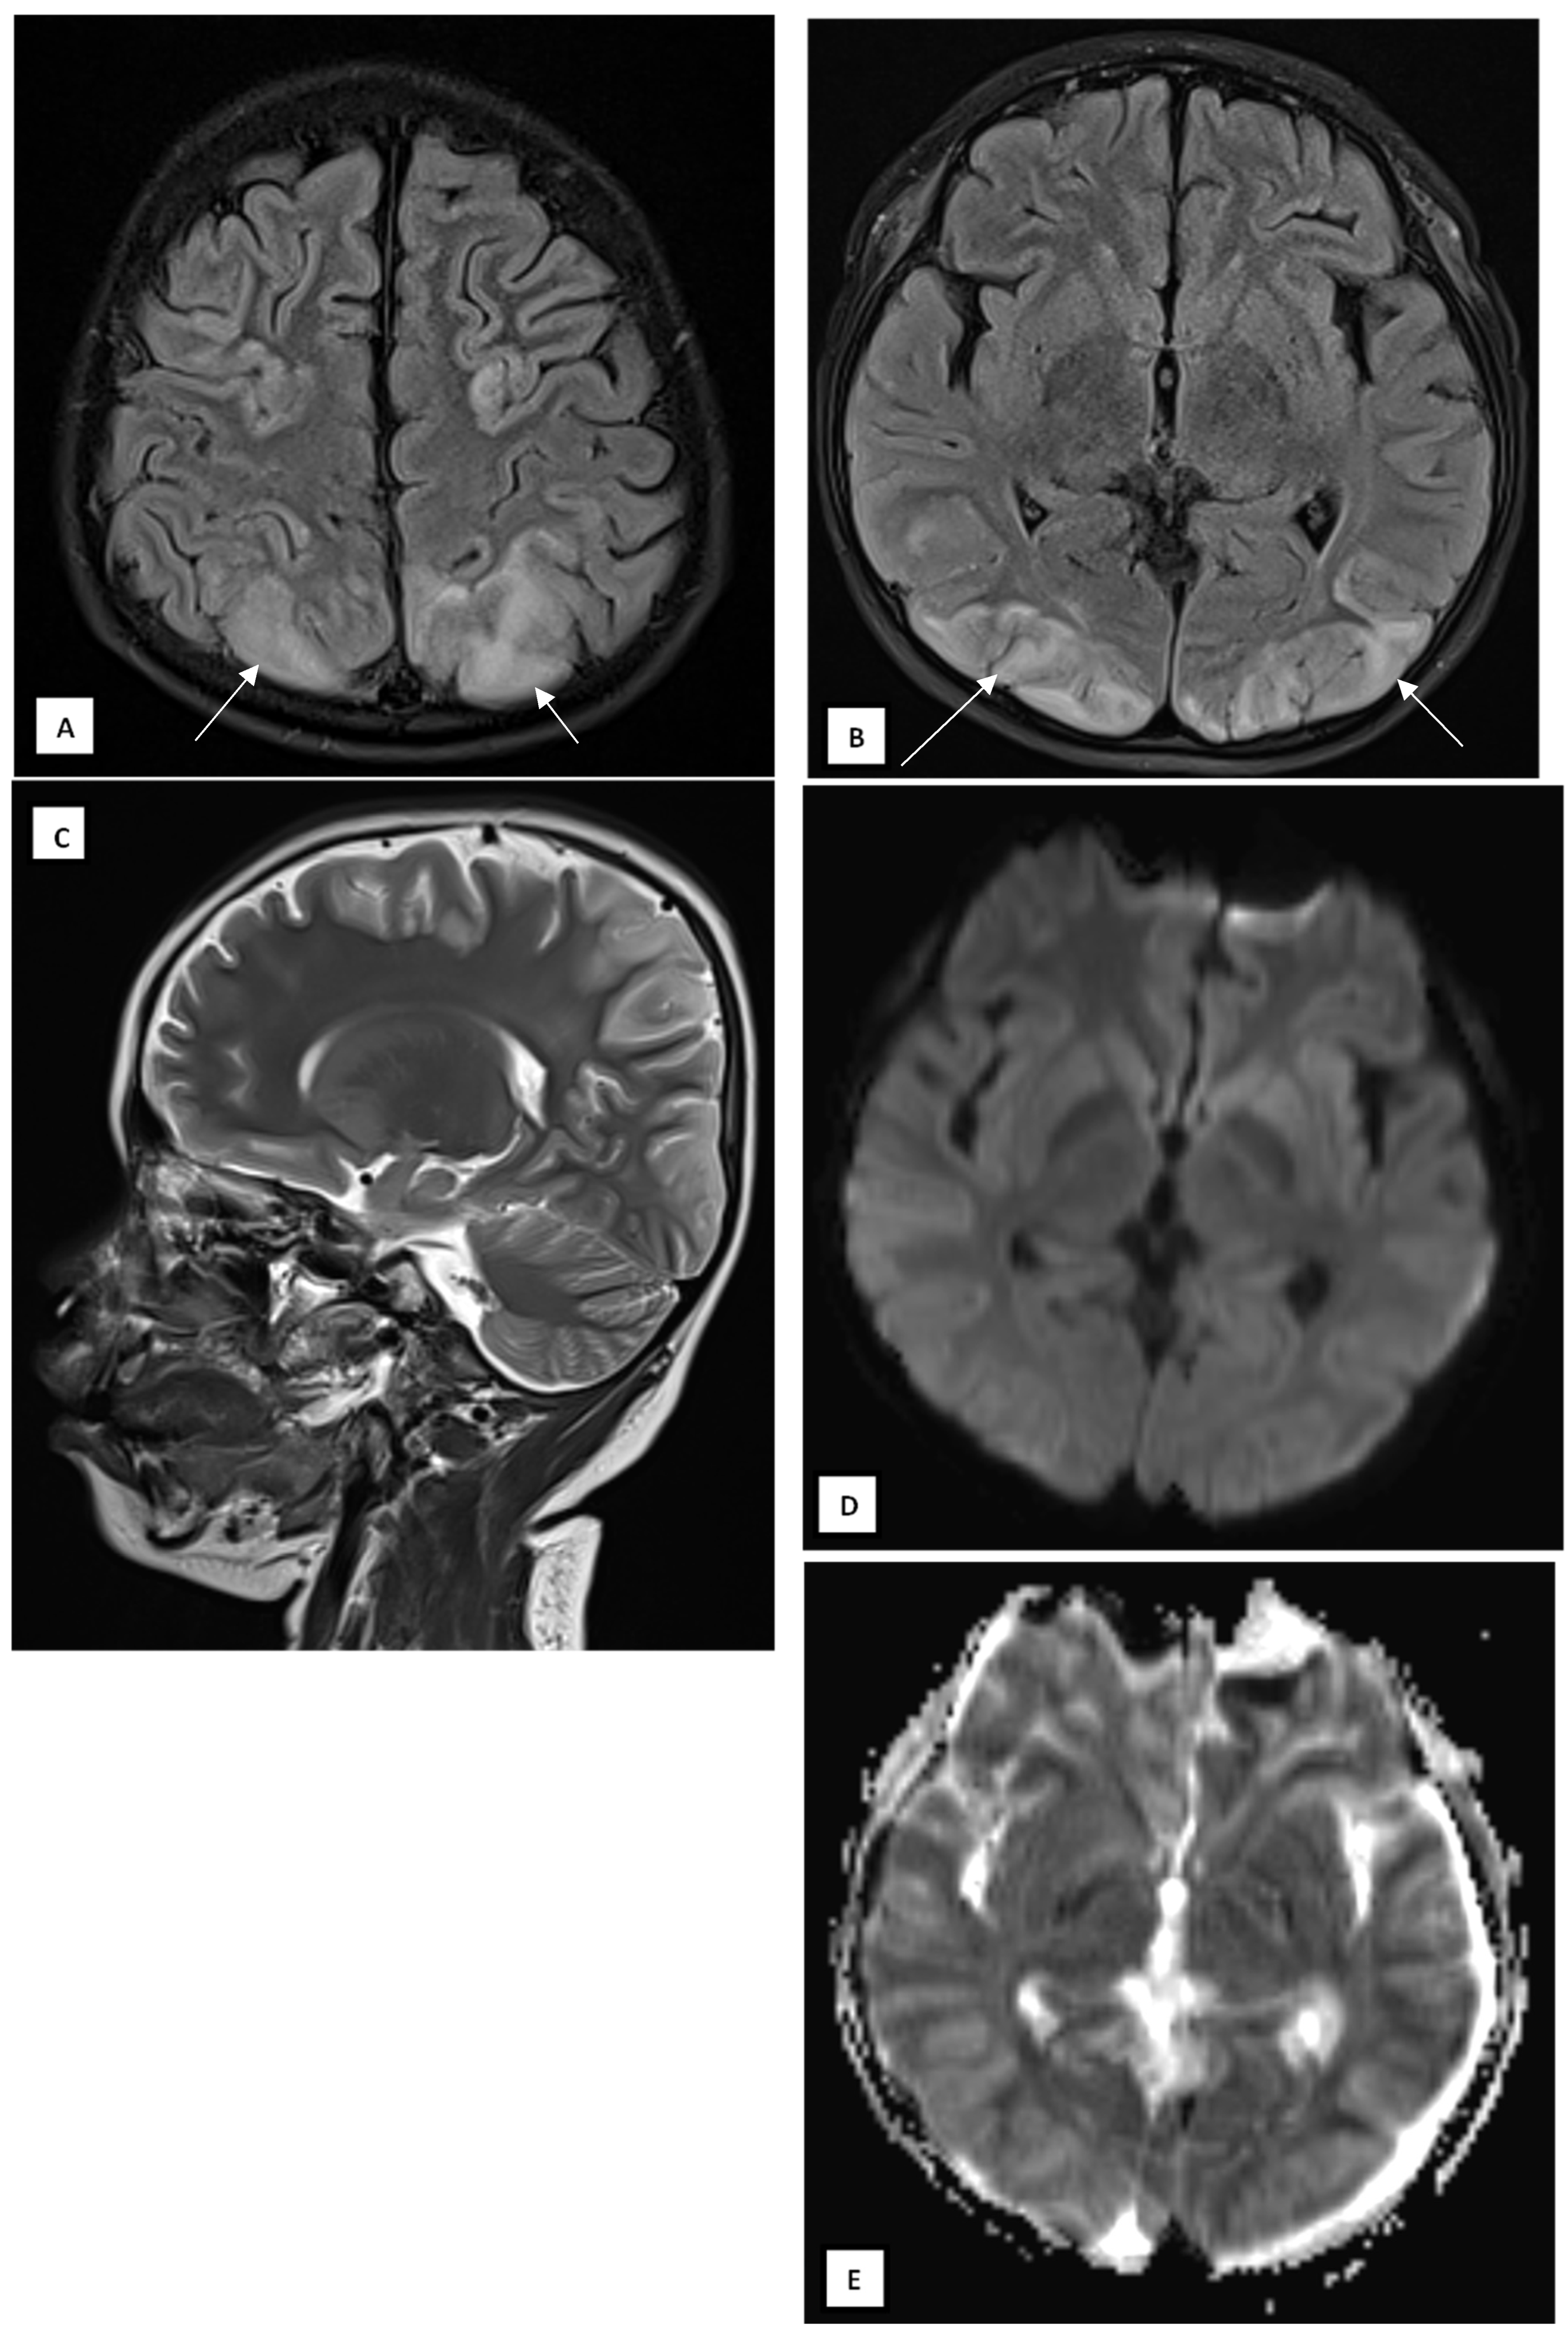

Over the next 48 h, the patient’s consciousness fluctuated, with a GCS deteriorating to E2M4V2. There were no significant changes in laboratory parameters. Brownish aspirate from the NGT prompted the discontinuation of dexamethasone. On day 5 of illness, a contrast-enhanced head CT scan was performed to evaluate for meningoencephalitis, which showed no abnormalities (Figure 1A,B).

Figure 1. A 10-year-old boy presented with visual disturbance and seizures. Axial non-contrast (A) and axial contrast-enhanced (B) head CT scans showed no evidence of meningoencephalitis, with findings within normal limits.

This case highlights that PRES is associated with reversible neurological complications in MIS-C. The temporal sequence, systemic inflammation, transient hypertension, seizures, and visual loss match the classic presentation of PRES [1,2]. MRI confirmed bilateral parieto-occipital and posterior temporal cortical–subcortical hyperintensities, consistent with vasogenic edema rather than cytotoxic injury. The normal CT findings emphasize the superior sensitivity of MRI in detecting PRES [5].

Brain imaging, particularly MRI, plays a critical role in diagnosing PRES by revealing characteristic patterns of vasogenic edema, although findings can vary widely [9]. The three primary MRI patterns, which are dominant parieto-occipital, holohemispheric watershed, and superior frontal sulcus, account for approximately 70% of cases. These patterns typically show bilateral but often asymmetric subcortical white matter involvement, frequently accompanied by cortical changes [5]. Incomplete or atypical presentations are also common, including partial or asymmetric expression of these patterns, often with patchy or linear edema in the frontal lobes [11]. Beyond these classic areas, atypical findings may involve the frontal and temporal lobes (seen in up to 75% of cases), basal ganglia and brainstem (up to one-third), and cerebellum (up to half), usually alongside parieto-occipital involvement. Less commonly, restricted diffusion is observed in 15–30% of cases, typically representing irreversible injury. Intracranial hemorrhage, which is the most frequent intraparenchymal or sulcal subarachnoid hemorrhage, occurs in 10–25% of patients and is associated with anticoagulation or coagulopathy. Additionally, contrast enhancement may be seen in about 20% of cases [2,5]. Vascular imaging (MRA or catheter angiography) has shown vasoconstriction in 15–30% of cases, most notably in the posterior circulation, though higher rates have been reported in selected studies. CT scans may show edema in some cases, but MRI, particularly T2-weighted FLAIR sequences, remains more sensitive and is preferred for accurate detection and characterization of PRES [2]. In both this systematic review and our case report, CT scans did not reveal any abnormalities, suggesting that CT may lack the sensitivity required to detect PRES or that its diagnostic utility is highly dependent on timing, with greater effectiveness if performed during the acute phase of the condition [5].

This case expands the limited literature linking PRES and MIS-C [4]. It also demonstrates that CT alone may fail to reveal early edema, underscoring the importance of MRI when neurological deterioration occurs in MIS-C patients [5].